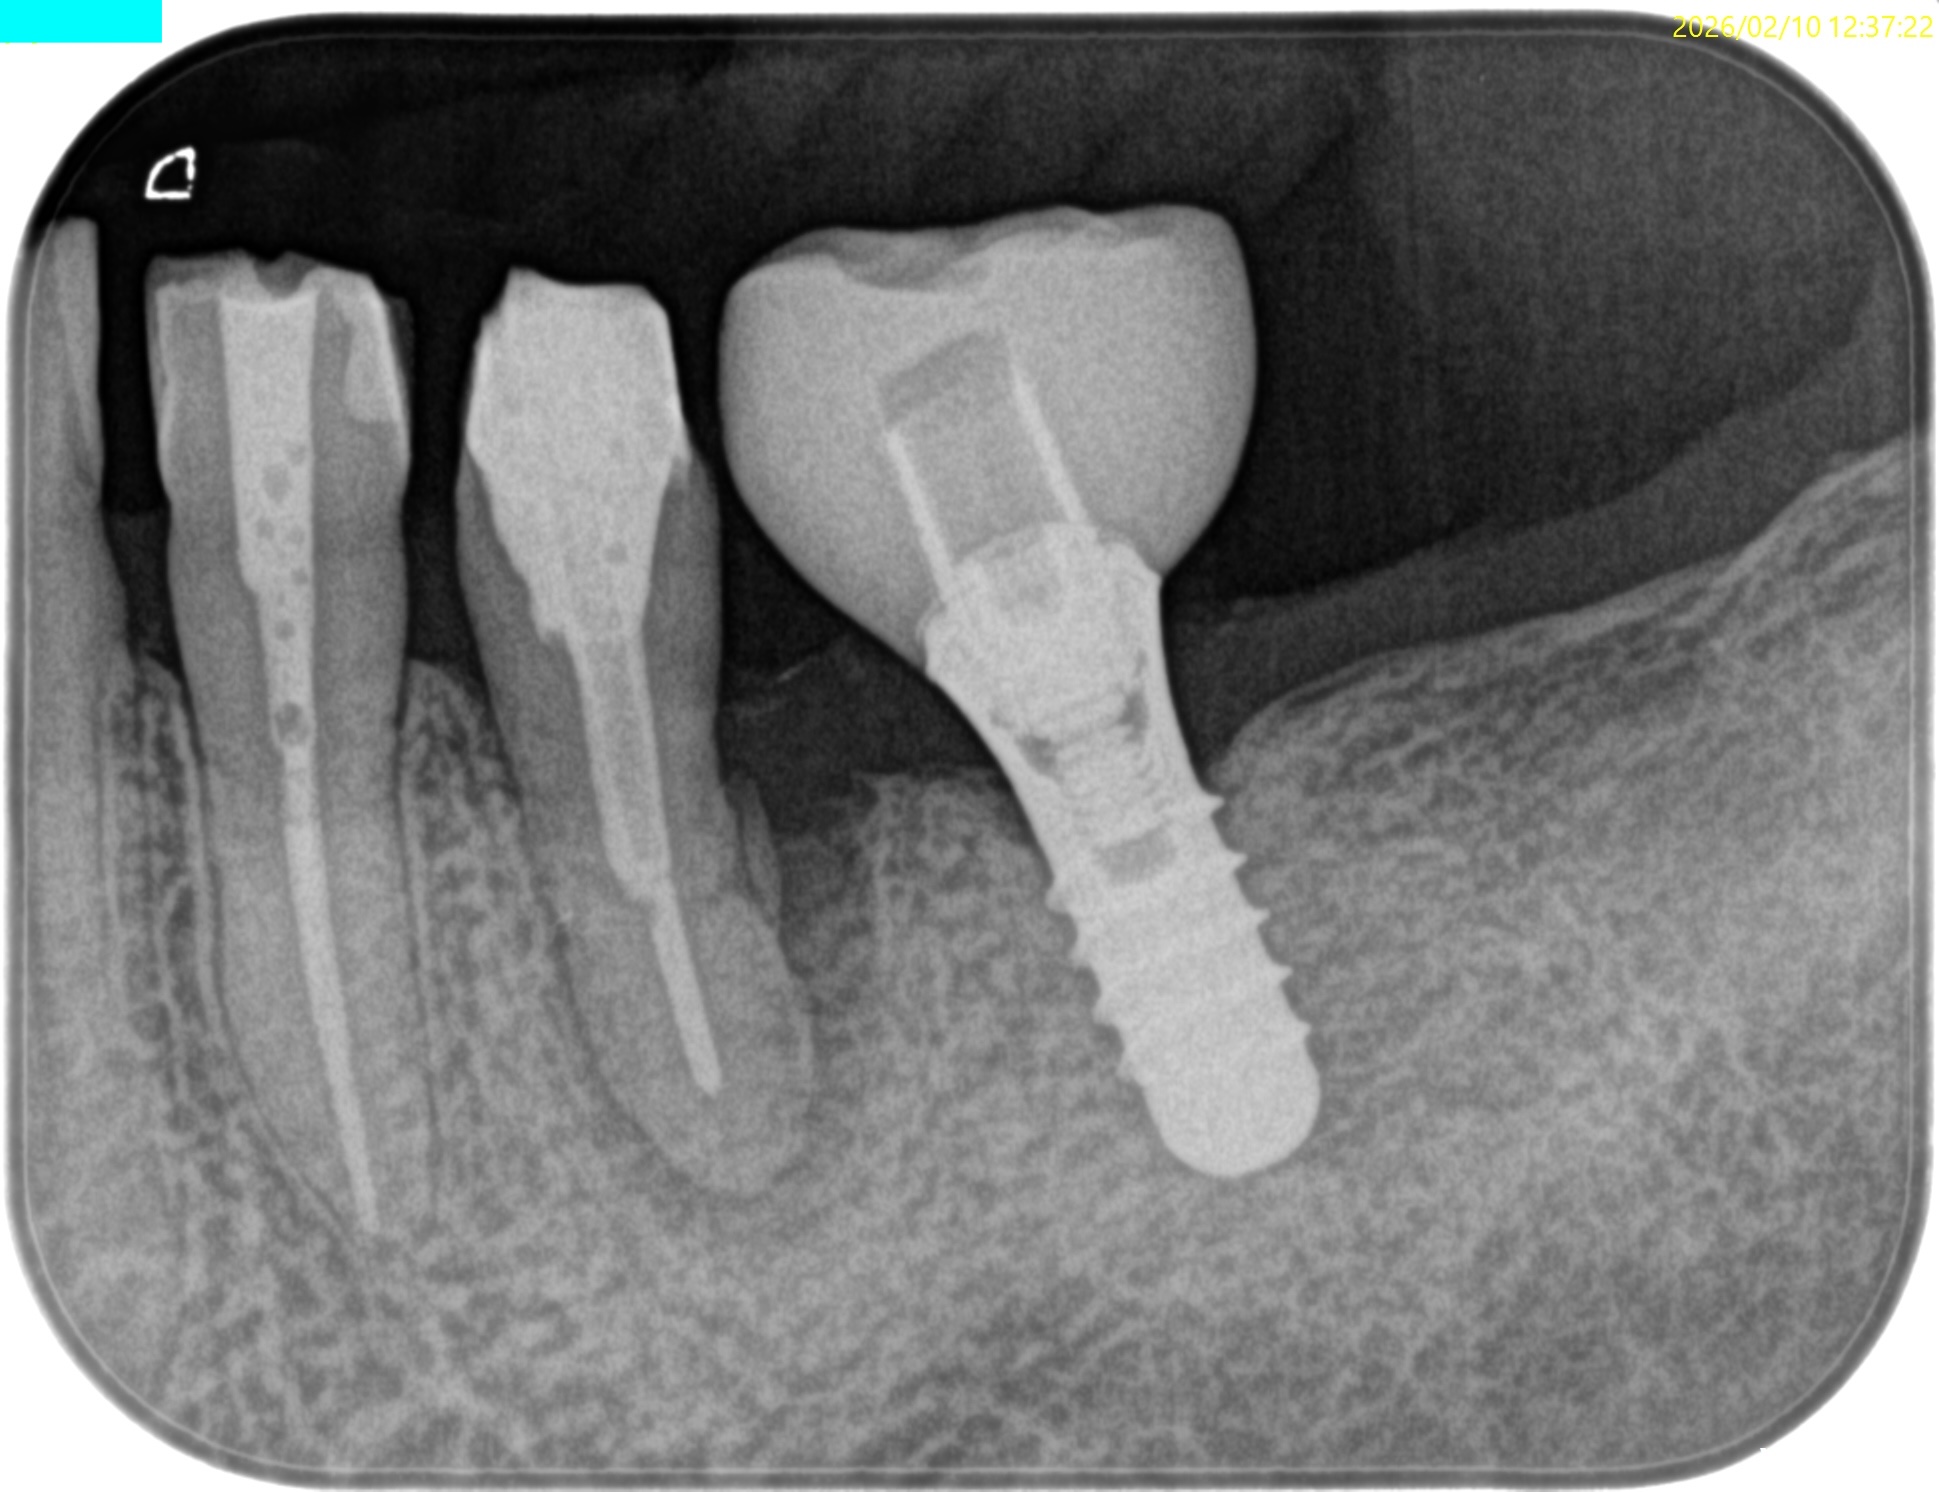

この後、ようやくコア用レジンとFiber Postで築造し、術後にPAを撮影した。

見事スクリューピンを除去し支台築造した。

この後、#20にはIntentional Replantationが行われるがその模様はまた後日お伝えしよう。